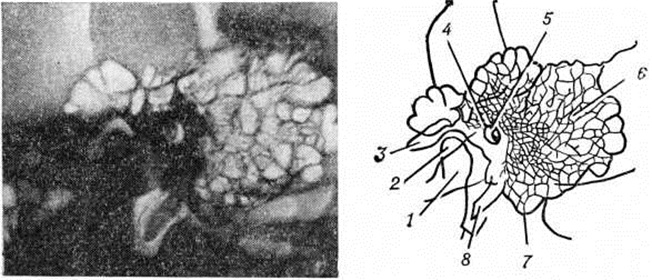

Классическим методом рентгенологическое исследования сосцевидного отростка является предложенная Шюллером (A. Schuller, 1905) рентгенография височной кости в боковой проекции (рисунок 1), а также предложенная Стенверсом (Н. W. Stenvers, 1928) рентгенография сосцевидного отростка в косой проекции (рисунок 2). Рентгенологические картина начальной экссудативной стадии острого Мастоидит характеризуется только затемнением сосцевидных ячеек; симптомы нарушения костной структуры отсутствуют. Резкое понижение воздушности ячеек приводит к снижению естественной контрастности снимка и затрудняет выявление тончайших костных перекладин между ячейками височной кости. В пролиферативно-альтеративной стадии Мастоидит с выраженным разрушением перекладин сосцевидных ячеек на рентгенограмме обнаруживается значительная потеря интенсивности линейных теней перекладин, а местами почти полное их отсутствие. При гнойном расплавлении перекладин и образовании абсцесса в сосцевидном отростке определяется очаг разрежения костной ткани. Очаг костной деструкции некоторое время может сохранять на рентгенограмме трабекулярную структуру, что объясняется наличием сохранившихся ячеек, окружающих полость абсцесса. При образовании субпериостального абсцесса с полным разрушением костной ткани просветление от деструктивного очага становится интенсивным и бесструктурным (рисунок 3). В период сохранения трабекулярности в области абсцесса, особенно небольшого, рентгенологическое распознавание его может представлять значительные трудности. Полость такого абсцесса в хорошо развитом пневматическом сосцевидном отростке ясно видна на томограммах височной кости.

Рис. 2. | ||